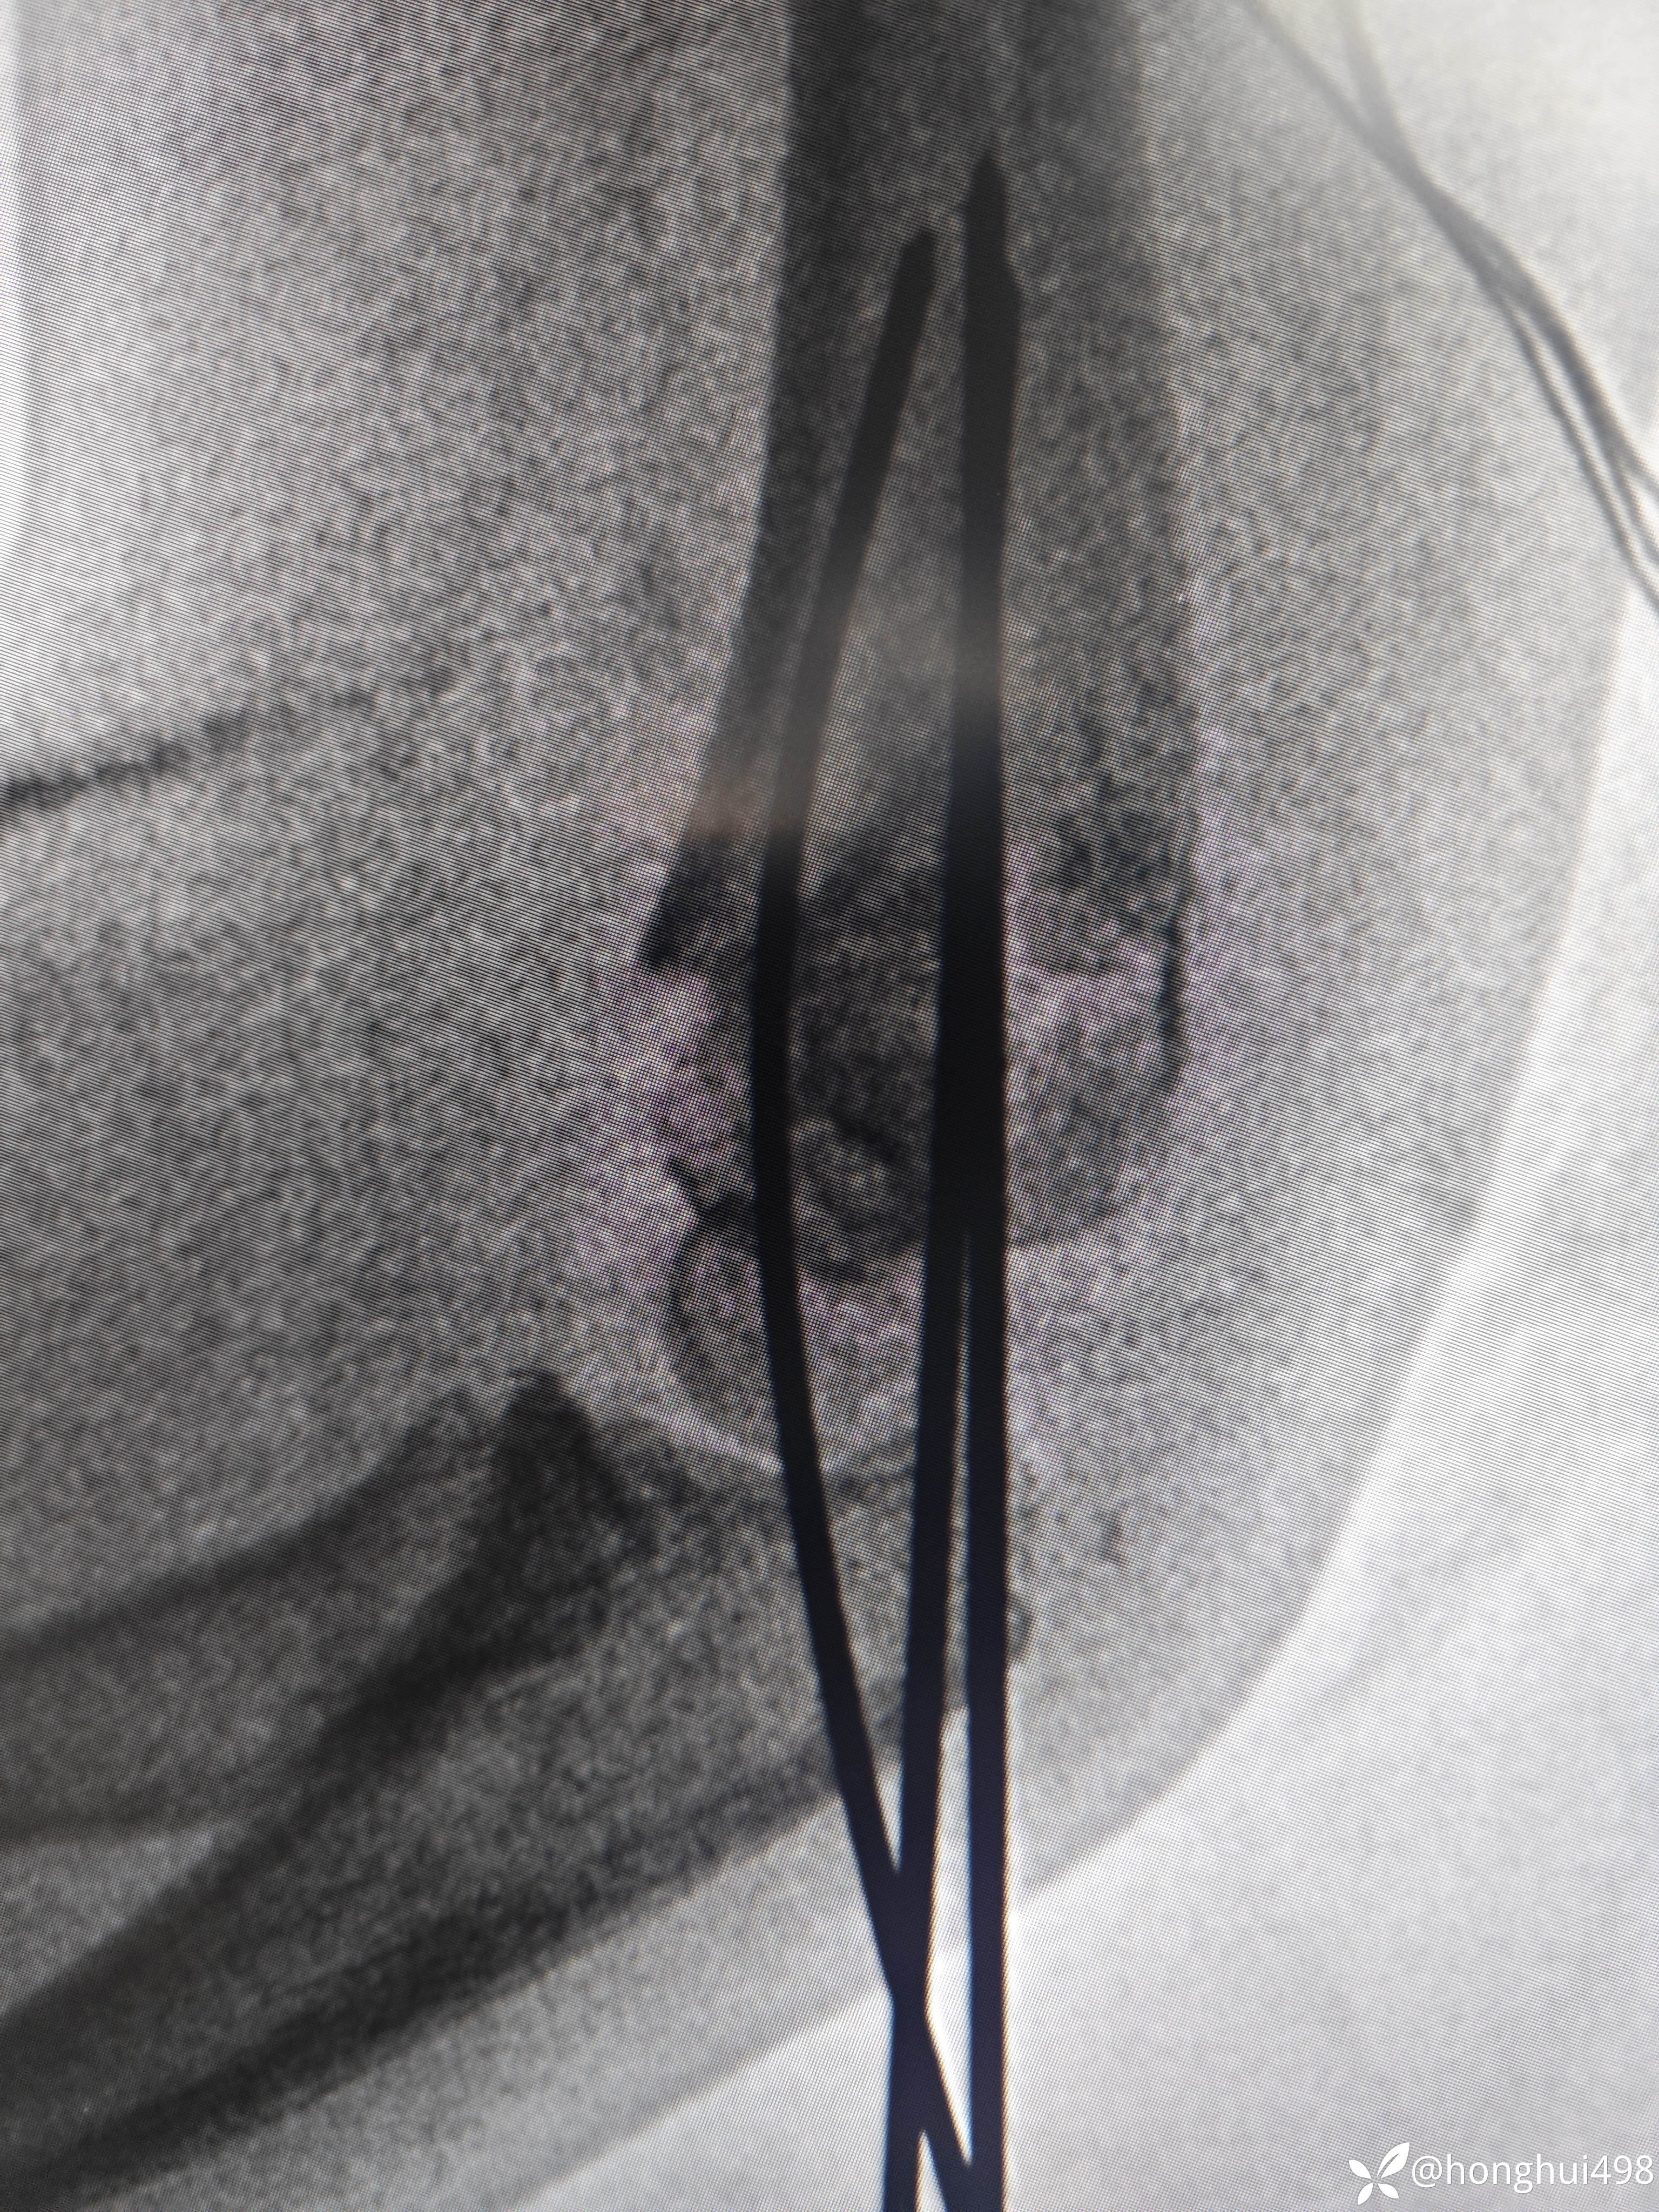

患儿女性,6岁,昨晚8点在家玩耍摔倒受伤,右肱骨髁上骨折。伤后在当地予手法复位草药外敷,伤后15小时来我院就诊,住院麻醉下闭合复位克氏针内固定。